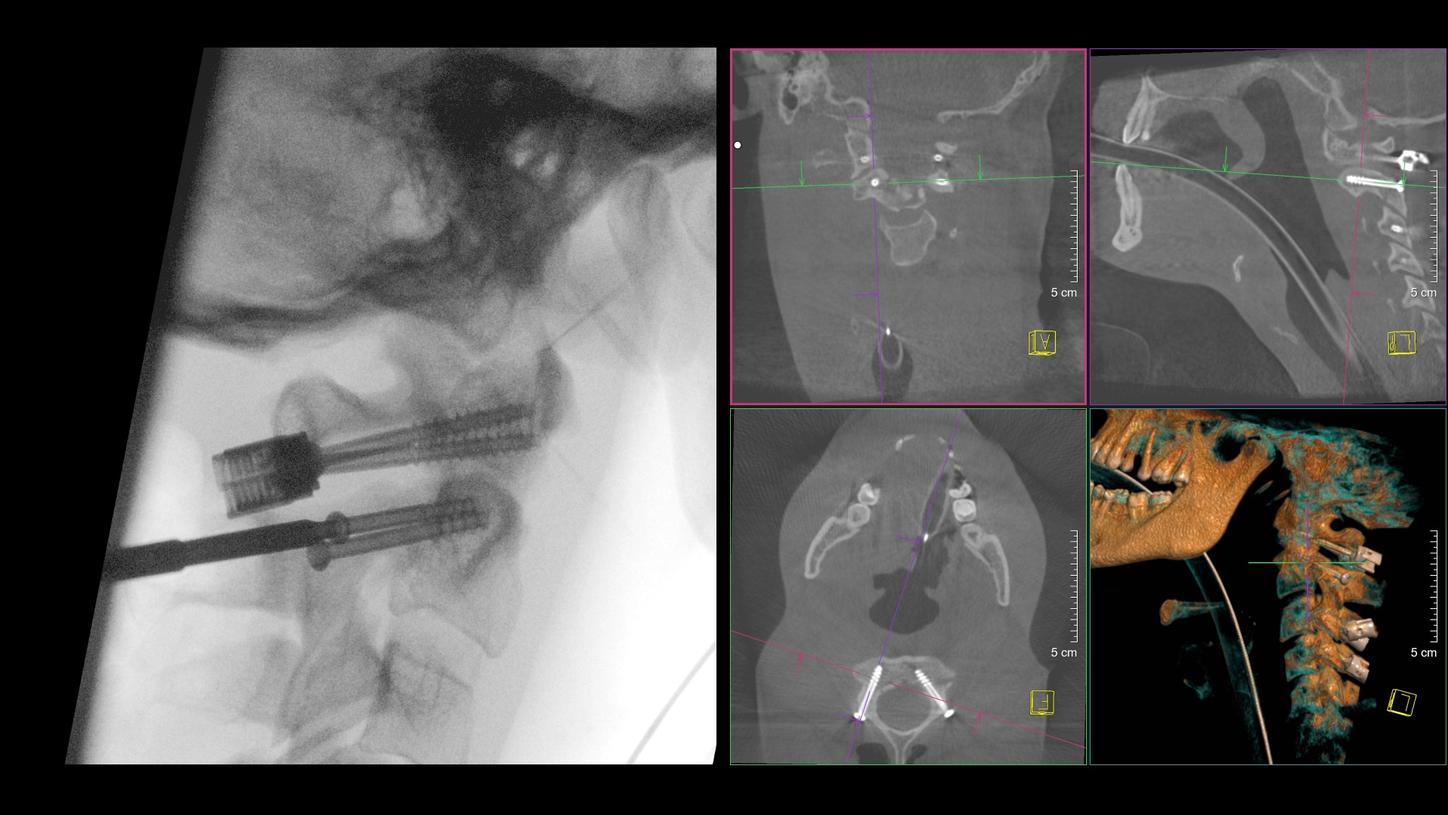

Benefit from precise 2D and 3D visualization of anatomical structures and metallic objects with excellent image quality.

Screw Scout

Yes2

Navigation interface

NaviLink 3D2